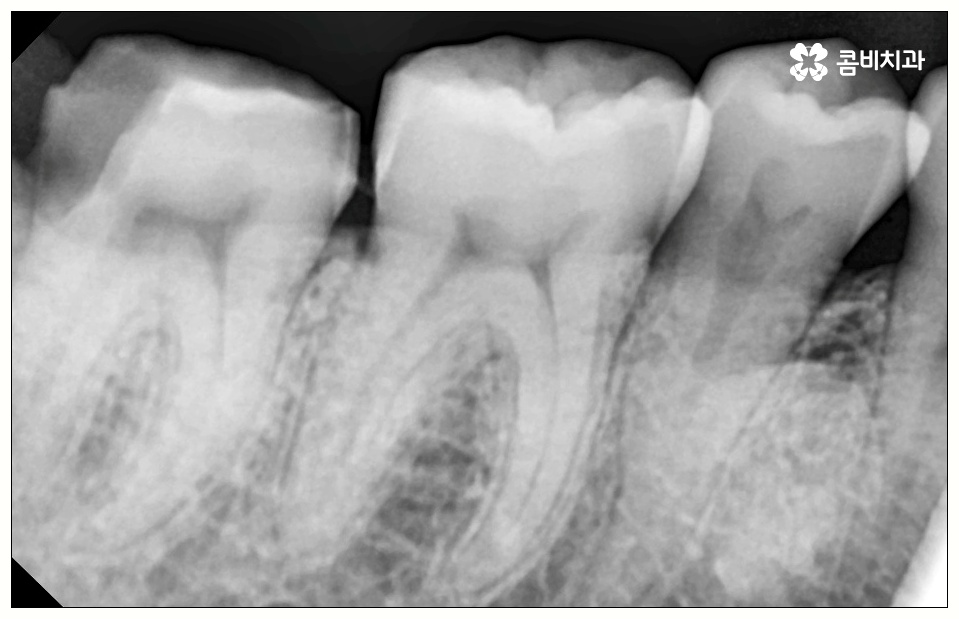

하지만 꼭 발치 처치를 받아야 하는 사랑니도 있는데 그 중 대표적인 것이 바로 어금니 사이 충치 를 유발한 경우로, 비스듬하게 나온 사랑니가 앞의 어금니를 밀면서 압박을 주고 옆면에 충치를 일으키는 등 손상시키고 있다면 늦기 전에 발치 처치를 받으실 필요가 있습니다.

이 때 어금니 뒤쪽으로 비스듬하게 사랑니가 자리를 잡으면 부분적으로 맹출이 되면서 치아 사이에 좁은 틈새가 만들어져 여러 가지 부산물들이 끼기 쉬워지는 반면 칫솔질 등 관리는 더욱 어려워지기 때문에 구강 질환 발생률이 높아질 수 있어요.

특히 어금니 사이 충치 는 눈에 잘 보이지 않을 뿐만 아니라 어느 정도 진행이 될 때까지 통증이 크지 않기 때문에 치료시기를 놓치게 되는 경우가 많이 있는데요.

이렇게 병증이 깊어지게 되면 치은에도 쉽게 손상이 일어나고 치아 내부 밀도가 떨어져 치아 파절이 일어날 수 있으며 결국 사랑니만 뽑는 것이 아니라 저작 기능에 중요한 역할을 하는 어금니까지 발치해야 하는 상황이 생길 수도 있기 때문에 초기에 잘 대처하실 필요가 있어요.

치아 사이 충치는 법랑질이 두꺼운 교합면, 즉 음식을 잘게 부수는 윗면이 아니라 치아와 치아 사이에 맞닿고 있어 비교적 법랑질의 두께가 얇고 신경까지의 거리가 짧은 옆면에 생기는 것이기 때문에 병증이 진행되는 속도가 빠르고 치료하기가 까다로워 될 수 있는대로 빨리 대처하실 필요가 있어요.